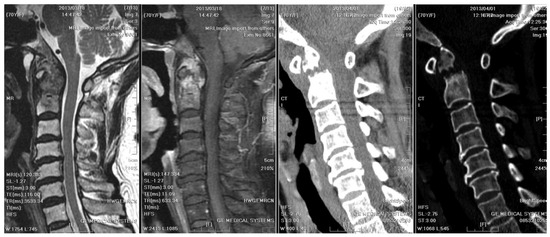

A radiographic examination of the cervical spine identified bony destruction of the C2 odontoid process and C1–C2 subluxation (Figure 1). Subsequent MRI with contrast enhancement and CT revealed an osteolytic lesion at C2, along with prevertebral and paravertebral soft tissue infiltration (Figure 2). The patient was suspected to have osteomyelitis, spinal tumor, or Langerhans cell histiocytosis. Prophylactic antibiotics cefazolin and metronidazole were administrated for one day prior to surgery.

Figure 2. Initial MRI and CT of the cervical spine: They revealed an osteolytic lesion at C2, along with prevertebral and paravertebral soft tissue infiltration. Mild spinal canal stenosis was observed, while the diameter of the spinal cord was within an acceptable range. Bony destruction of C2 odontoid process and atlantoaxial subluxation were identified. Heterogeneous contrast enhancement of vertebral body and subligamentous spread at prevertebral area were observed. The wall of abscess was ill-defined, smooth, and regular. However, the thickness of the wall was equivocal.